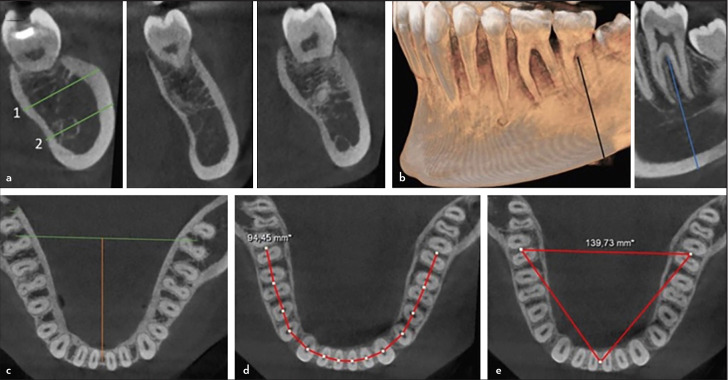

Objective: This study aimed to examine the mandible form features of the mandible, such as inter-second molar width, anteroposterior length, arch perimeter length, arch breadth, corpus height/width in the mandibular second molars (MnSM) region, and arch form, and the relation for the occasion of the 1-rooted/C-shaped.

Methods: The study analyzed cone-beam computed tomography images of 215 male and 215 female Turkish patients to determine the prevalence of 1-rooted and C-shaped MnSM. Mandibular dentoalveolar characteristics of individuals with bilateral (1R-1R group) and unilateral (1R-2R group) 1-rooted MnSM were examined and compared with those with bilateral 2-roots (2R-2R group) MnSM. Statistical tests were performed using Chi-square, one-way ANOVA, Tukey, and binary logistic regression analysis at the 5% significance level.

Results: The prevalence of 1-rooted and 1-rooted/C-shaped MnSM was 12.79% and 9.65%, respectively. Root fusion was more commonly present in females (p<0.05). In the 1R-1R group, the anteroposterior length was shorter than in the 2R-2R group (p<0.05). There was no difference between the groups for other features (p>0.05).

Conclusion: Although the study found a shorter anteroposterior length in the 1R-1R group, no feature was a predictive variable for 1-rooted/C-shaped MnSM.